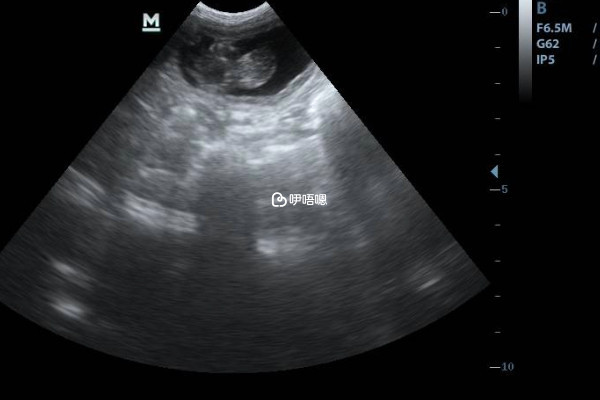

孕9周有了胎心胎芽,胎停的機率就比較小了,但也不能說完全沒有,機率大概10%以下。通常情況下,隨著孕期的增加,胎停育的機率就會逐漸降低,如果到了9周還出現胎停,就有可能是因為母體的原因,比如孕媽母體孕酮不足、生殖器發育畸形、內分泌異常或者接觸環境汙染等因素,還有可能是胚胎自身的問題,常見的有染色體異常、胚胎質量不好等因素,導致其不能正常生長髮育。

雖然孕9周出現胎停的機率比較小,但是孕媽媽也要引起重視,尤其是在孕早期,即使出現了胎心胎芽也是有可能會出現胎停育的,因為孕期前3個月時,母體需分泌大量孕激素、雌激素、黃體酮等,來支援胎兒的生長髮育,若母體出現黃體酮,或雌、孕激素分泌異常,均可導致有胎心後胎停。下面就介紹一下孕早期不同孕周的胎停機率,如下: